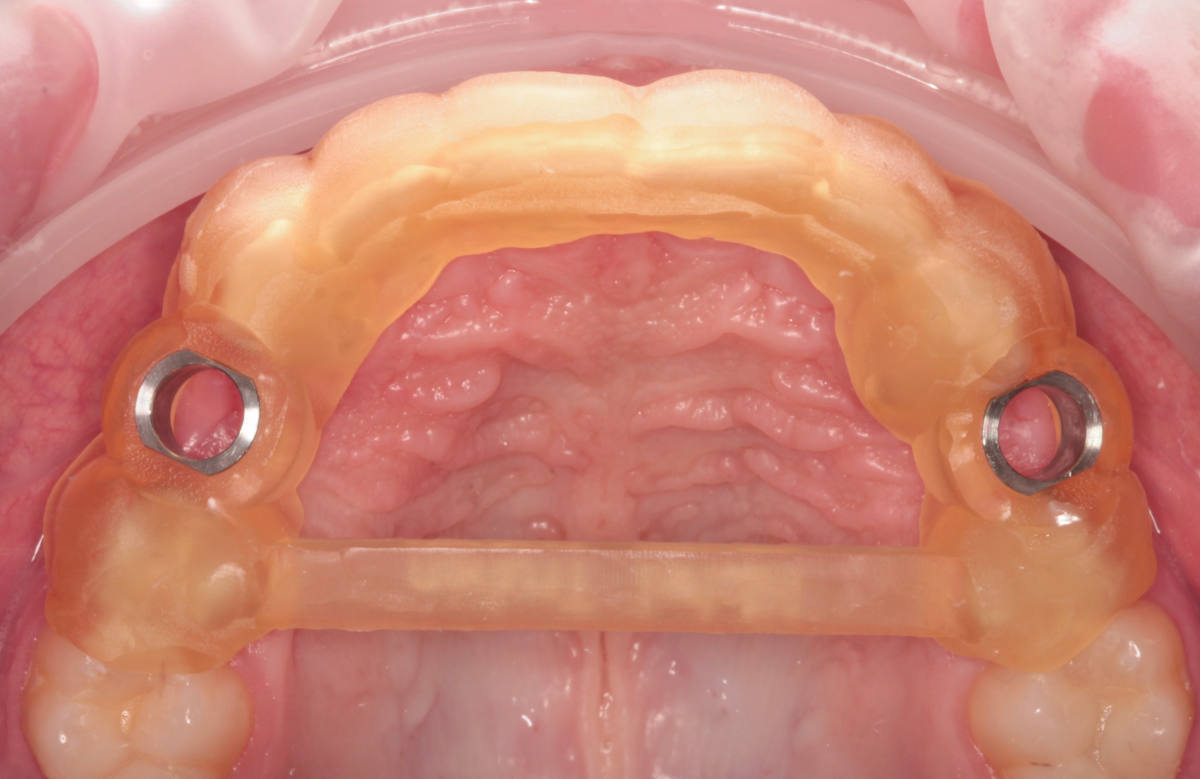

Navigovaná chirurgia, 3 implantátov

Autor práce Dr. Michal Repaši

Zubný technik Vasil Csopej